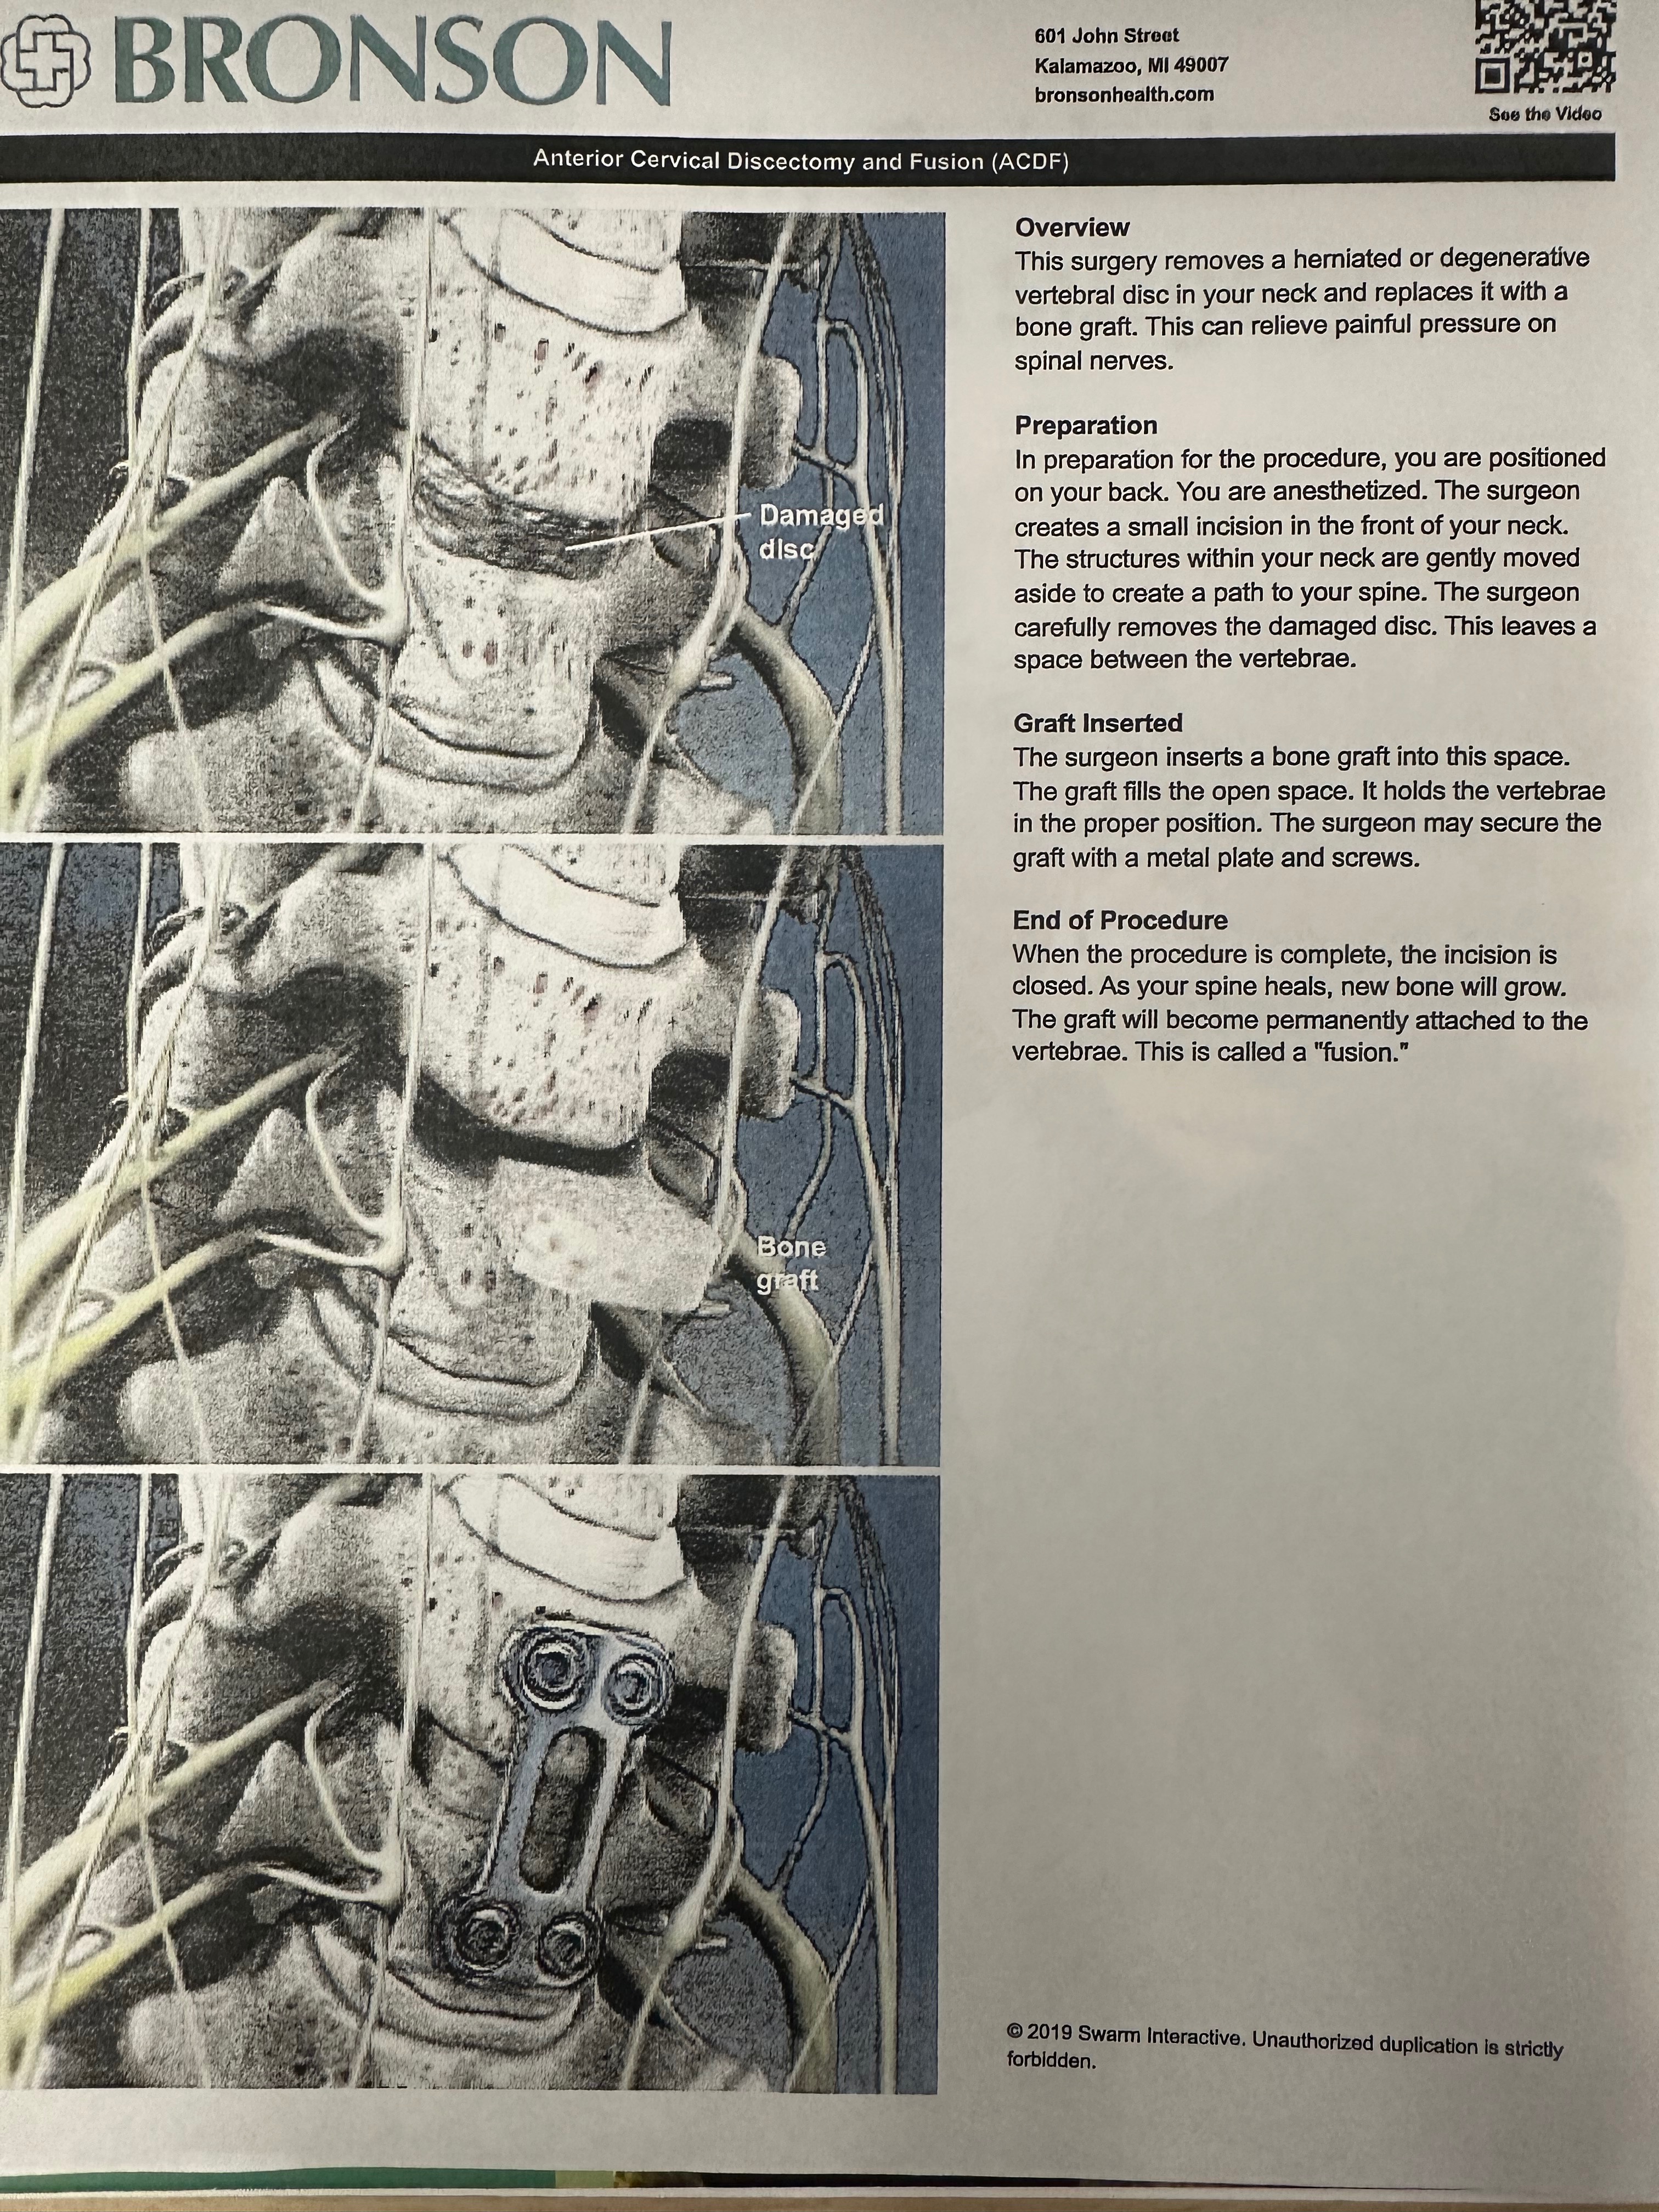

For over a year, I've had a pain in my neck and right shoulder blade. I thought I pulled something. Fast forward to May of this year. X-rays showed a narrowing of my cervical spine. I was sent to physical therapy. After 8 weeks of no relief, the PT recommended I have a follow-up appointment with my primary provider. Then they ordered an MRI. The results showed nerve damage caused by the degeneration of my C6-C7. I was then referred to a neurosurgeon at Bronson Methodist. The neurosurgeon recommended a fusion surgery that will most definitely help me. My surgery is scheduled for October 7.